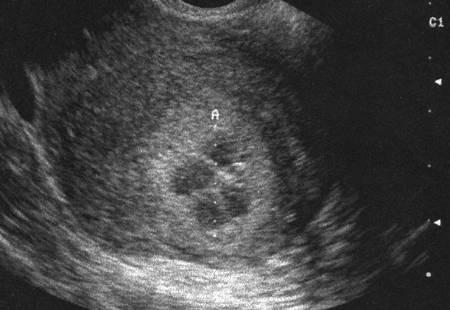

Myome en nécrobiose (Cliché : Dr. C. TALMANT)